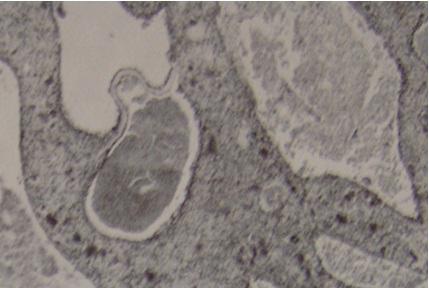

MRI and CT showed fluid in the bone (Figure. 2). Arthroscopic curettage without bone grafting was performed. A 6-mm skin incision was used to aspirate the bloody fluid and remove the cyst membrane (Figure 3). Pathologic examination demonstrated the cyst to be an ABC (Figure. 4). Curettage was performed using the arthroscope. Range of motion exercices were begun on the first postoperative day. The outcome was good and there was no evidence of recurrence at the 20-month follow-up (Figure. 5).

Figure 4: Typical histological features of the aneurismal bone cyst. The cells lining the cystic spaces are not endothelial.